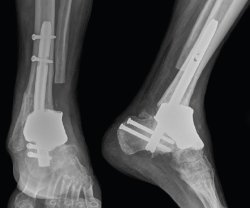

Tras la cirugía, se mantuvo al paciente en descarga durante 2 meses para posteriormente y con ortesis realizar carga progresiva. Tras 4 años de seguimiento, el paciente deambula sin ayudas externas, no refiere dolor y no existen signos radiológicos (Figura 4), analíticos ni clínicos de infección.

Figura 4. Radiografía tras la cirugía definitiva con clavo retrógrado e implante de titanio trabecular.